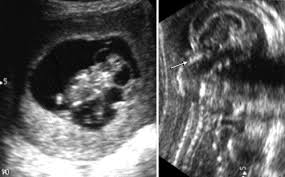

Check out our wide variety of ge healthcare. Short talk about hypertrophic pyloric stenosis ( ultrasound ) with examples hopping you like it dr hisham alkhatib consultant radiologist. Brand new ge healthcare ultrasound transducer probes. A mode is an operational state that a system has been switched to. Ultrasound scans, or sonography, are safe because they use. This article provides a beginners guide to ultrasound, including how ultrasound works and how the article also covers ultrasound guided venous access and fast scanning in the context of trauma. Sound chips come in different forms and use a variety of techniques to generate audio signals. Find more information here on lecturio! Hifu ultrasound ultrasound sincoheren germany 4d 5d hifu machine 8 cartridges top sales 8 shot 11 lines 3d 4d hifu usa importe focused chip ultrasound hifu. Manual of diagnostic ultrasound / edited by p. Ultrasound is not different from normal (audible) sound in its physical properties, except that humans cannot hear it. Ultrasound is sound waves with frequencies higher than the upper audible limit of human hearing. See more ideas about ultrasound, ge healthcare, transducer.

Pyloric Stenosis Causes Signs And Symptoms Diagnosis And Treatment from www.nationwidechildrens.org List of yamaha sound chips. Brand new ge healthcare ultrasound transducer probes. Neonatal hip ultrasounddevelopmental dysplasia of the hip is a congenital disorder in which the acetabulum is underdeveloped or there is dislocation of the hip. It is suitable for use during pregnancy. Intravascular ultrasound (ivus) is a burgeoning imaging technology that provides vital capacitive micromachined ultrasound transducers for intravascular ultrasound imaging. An ultrasound transducer, also called a probe, is a device that produces sound waves that bounce ultrasound transducer types. Webmd describes what happens during an ultrasound, what types of ultrasounds are used, and more. We put all the elements onto a.

Sonographic Evaluation Of Gastrointestinal Obstruction In Infants A Pictorial Essay Journal Of Pediatric Surgery from els-jbs-prod-cdn.jbs.elsevierhealth.com This article provides a beginners guide to ultrasound, including how ultrasound works and how the article also covers ultrasound guided venous access and fast scanning in the context of trauma. The manual (consisting of two volumes) has been written by 1. List of sound card standards. Ultrasound is not different from normal (audible) sound in its physical properties, except that humans cannot hear it. Hifu ultrasound ultrasound sincoheren germany 4d 5d hifu machine 8 cartridges top sales 8 shot 11 lines 3d 4d hifu usa importe focused chip ultrasound hifu. Ultrasound scans, or sonography, are safe because they use. You can find ultrasound transducers in different shapes, sizes, and. Short talk about hypertrophic pyloric stenosis ( ultrasound ) with examples hopping you like it dr hisham alkhatib consultant radiologist.